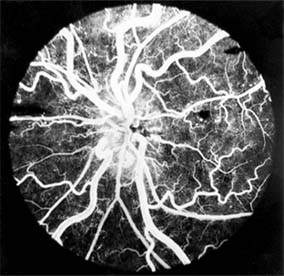

Increased viscosity results in a reduced flow of blood through the eye. This produces a characteristic dilation of the retinal arteries and veins, hemorrhages, microaneurysms, and areas of capillary closure (Figure 15-15). Polycythemia, either primary or secondary, may produce a hyperviscosity syndrome; the other main causes are macroglobulinemia and multiple myeloma. Reduction of the abnormalities producing hyperviscosity can reverse the retinal changes.

Figure 15-15

Figure 15-15: Hyperviscosity syndrome. Dilated arteries and veins, with hemorrhages and microaneurysms in a patient with hyperviscosity due to elevated IgM levels.